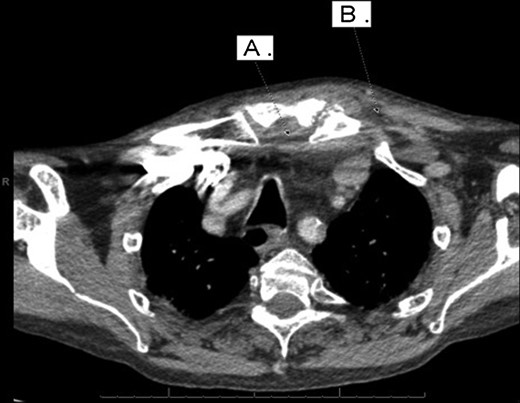

With a working differential of parapharyngeal space infection and possible malignancy, the patient was referred for a computed tomography (CT) scan of the neck and thorax with contrast. The patient was also started empirically on intravenous co-amoxiclav as treatment for neck space collection. CT imaging, performed 24 h after admission, revealed no evidence of malignancy or indeed any paraphayrngeal space collection. Few small lymph nodes were noted on the left side of the neck, but were deemed to be reactive in nature, and left vocal cord palsy was evident (Fig. 1). The key finding was that of a left sternoclavicular joint collection and closely associated superficial anterior chest wall, soft tissue swelling and oedema (Fig. 2). This inflammatory process was also noted deep to the manubrium and sternum and extending somewhat into the mediastinum with evident enlarged mediastinal lymph nodes (Fig. 3). The CT findings were in keeping with SSA with associated superficial and deep tissue inflammation and oedema. With no other cause found, the vocal cord palsy was attributed to the inflammation within the mediastinum, which in turn was caused by superficial burn from hot water bottle use.

Computed tomography. A 67-year-old male with SSA. Findings: soft tissue oedema of the chest seen retrosternally (marker A) and superficially on the left anterior chest (marker B) as well as evidence of mediastinal lymph node enlargement. Technique: contrast-enhanced axial CT of the neck and thorax.